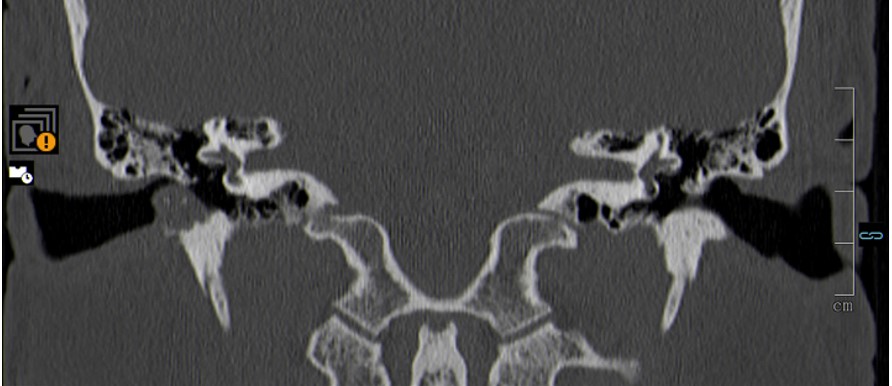

EAC cholesteatoma presents on CT as a sharply marginated expansile soft tissue attenuating lesion with bone erosions and small bone flecks within the lesion. These bone flecks are better visualized in narrow window width settings (Fig. 2).3

Figure 2: Coronal temporal bone CT image shows an EAC cholesteatoma as a soft-tissue mass in the inferior EAC, with associated erosion of the subjacent bone and small bone flecks inside the lesion.

In this case, the middle ear cavity and the facial nerve canal are uninvolved (3mm distance) and is classified as Stage I according to the CT classification system of Shin et al. (stage I - cholesteatoma of the EAC only; stage II: invasion of the tympanic membrane and the middle ear; stage III: involvement of the mastoid air cells; stage IV: lesions beyond the temporal bone).3

The management of the EAC cholesteatoma depends on the extent of the lesion, which should be assessed by CT. Canaloplasty is indicated for stage I lesions and it was performed in our case. Advanced stages may require a more radical approach with mastoidectomy or petrosectomy (Fig. 3).3

Figure 3: High-resolution CT of temporal bone in axial section depicts a lesion of the right EAC. Note the posterior bone erosion, without involvement of the mastoid air cells or the facial nerve canal (arrow).